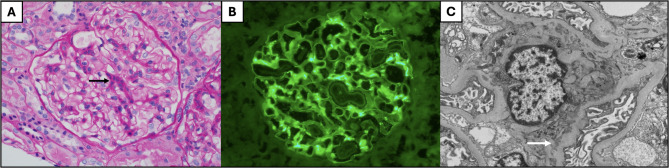

Case presentation: Case one is a 13-year-old male with asthma and allergies who presented with one month of cough and periorbital edema and subsequently developed submandibular swelling. Evaluation identified chronic sinusitis, weight loss, positive c-ANCA and anti-MPO IgG antibodies, peripheral blood eosinophilia, pulmonary eosinophilia, tracheal and pulmonary nodules, and eosinophilic infiltration of the submandibular salivary gland with granulomas and fibrosis fitting a diagnosis of EGPA. He improved with glucocorticoids and mepolizumab with a significant partial response, and eventually switched to benralizumab and mycophenolate mofetil with complete response. Case two presented at 19-months-old in acute respiratory distress with a history of reactive airway disease. EGPA diagnosis was confirmed on lung biopsy (eosinophilic capillaritis and interstitial expansion of eosinophils) in the setting of anti-MPO and p-ANCA positivity. He has done very well on mepolizumab for three years.